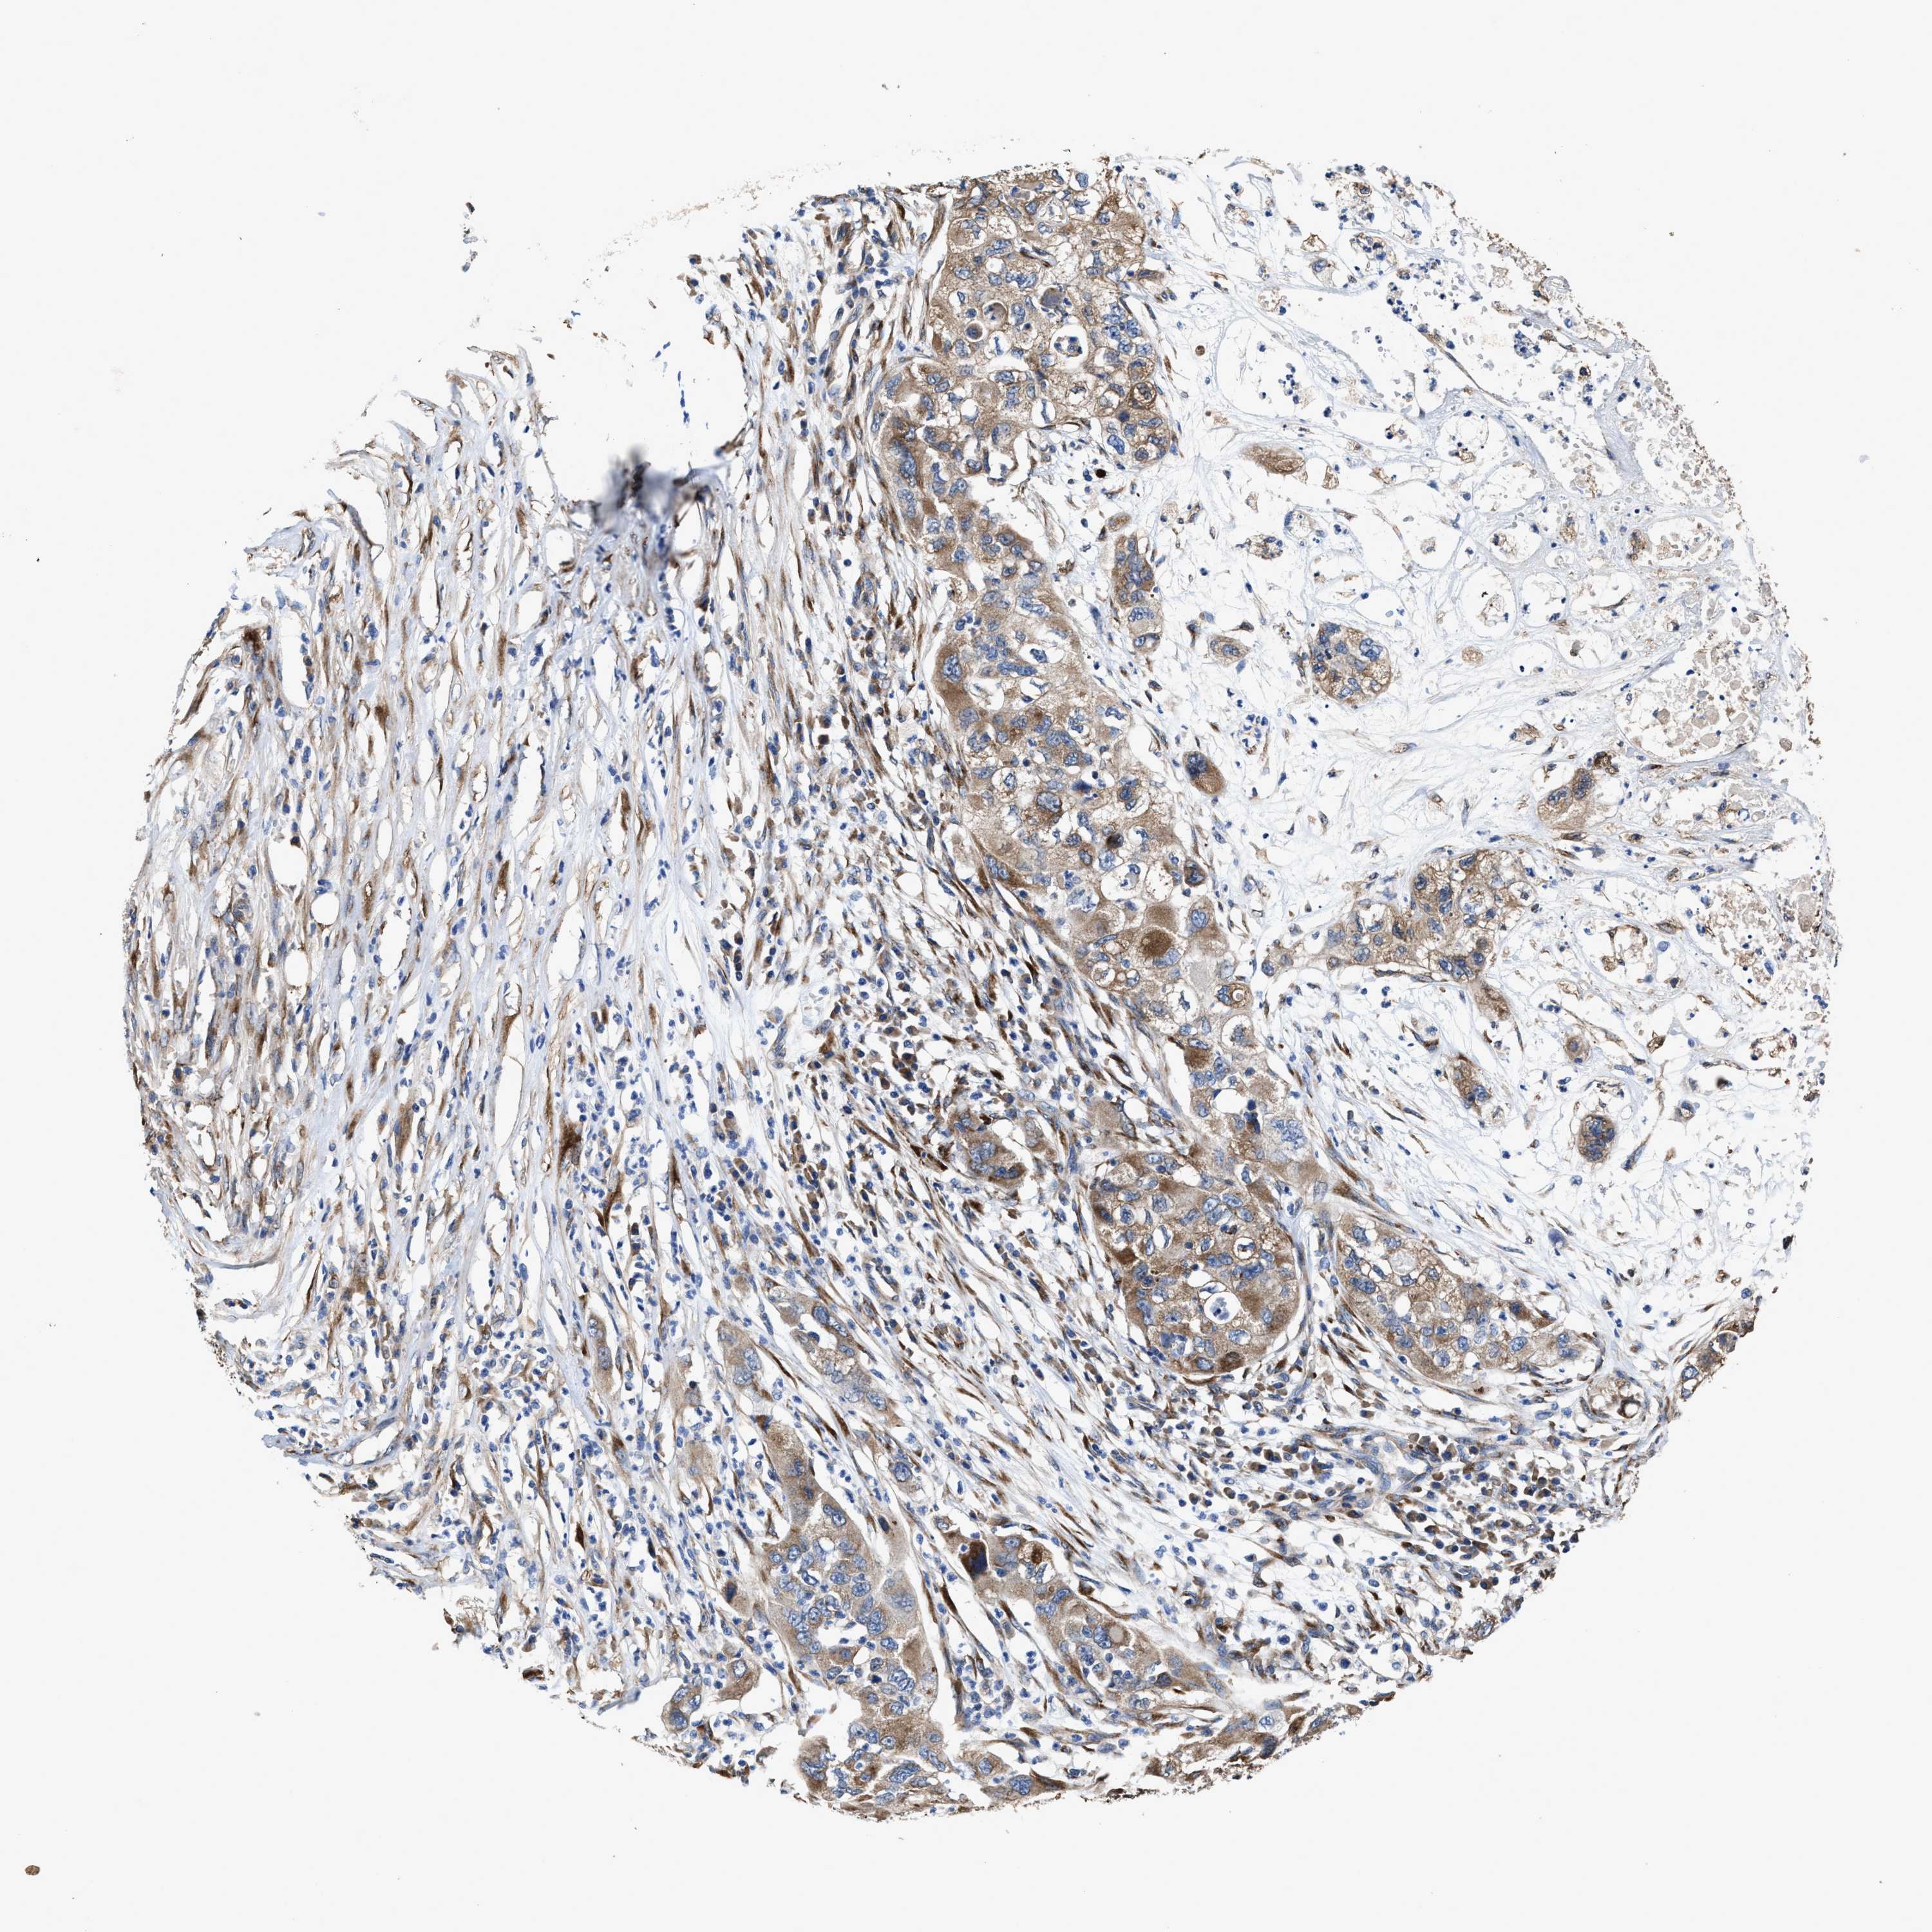

PANCREATIC CANCER - Protein expressioni

A mouse-over function shows sample information and annotation data. Click on an image to view it in a full screen mode. Samples can be filtered based on level of antibody staining by selecting one or several of the following categories: high, medium, low and not detected. The assay and annotation is described here.

Note that samples used for immunohistochemistry by the Human Protein Atlas do not correspond to samples in the TCGA dataset.

Antibody stainingi

Antibody staining in the annotated cell types in the current human tissue is reported as not detected, low, medium, or high, based on conventional immunohistochemistry profiling in selected tissues. This score is based on the combination of the staining intensity and fraction of stained cells.

Each image is clickable and will lead to virtual microscopy that enables deeper exploration of all samples and also displays staining intensity scores, fraction scores and subcellular localization as well as patient and tissue information for each sample.

Antibody HPA020378

Staining

High

Medium

Low

Not detected

Intensity

Strong

Moderate

Weak

Negative

Quantity

>75%

75%-25%

<25%

None

Location

Nuclear

Cytoplasmic/membranous

Cytoplasmic/membranous,nuclear

Adenocarcinoma, NOS